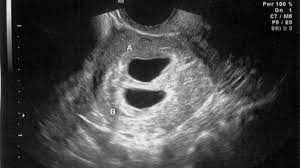

Ultrasound Accuracy For Predicting Due Dates

Ultrasound Accuracy For Predicting Due Dates from www.verywellfamily.com